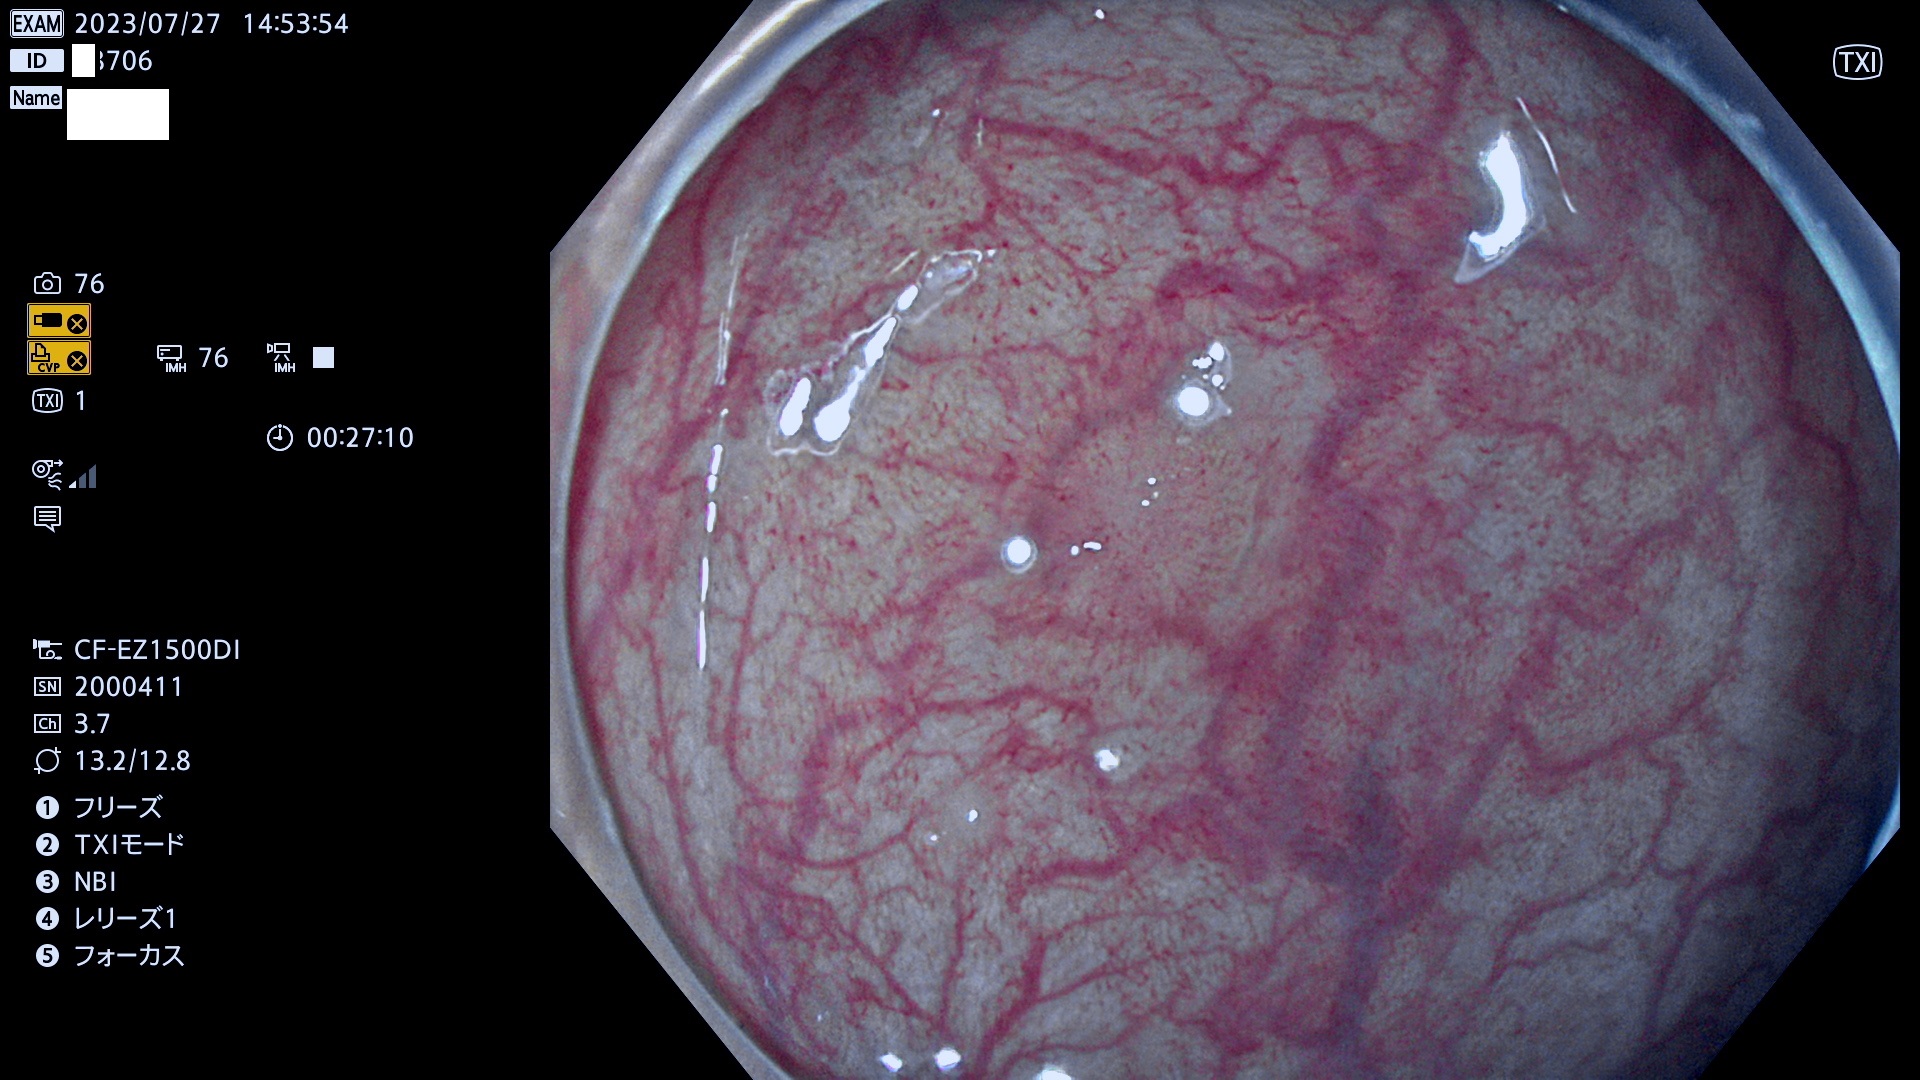

表面型腺腫(Flat Adenoma)の中で、完全に平坦な物をUb、陥凹している物をUcと呼びます。平坦隆起型(Ua)よりも、発見が難しく危険な病変です。このタイプは「内視鏡後・大腸癌の重要犯人」であり、この発見率は「腺腫発見率」よりも、重要な意味があります。

専門的)何故、陥凹していると危険? 癌遺伝子の変異が蓄積すると細胞分裂が盛んになり隆起するのでは?と通常は思われるでしょう。しかし実際は逆です。これは2022年の記事にある「細胞はストレスに直面したら細胞分裂を止める(細胞老化に入り休眠する)という生命の基本的現象」によるものです(Oncogene Stress)。細胞老化を起こすのが癌抑制遺伝子で、この安全装置(ブレーキ)が壊れると癌になります(休眠からの覚醒)。ですから陥凹は「まだ癌では無いが癌化の直前」を意味します。特に「小サイズなのに陥凹している」病変は短期間に腫瘍進化(⇒2021年記事)が起きたことを意味します(=ゲノム不安定性

毎週の検査(木・金・土・日)に発見されたUb、Uc型・腺腫を、その週の日曜の夜にUPし1週間、提示します。

抽出の対象期間 2023年7月27日(木)〜7月30(日)の4日間(48件の検査)11件